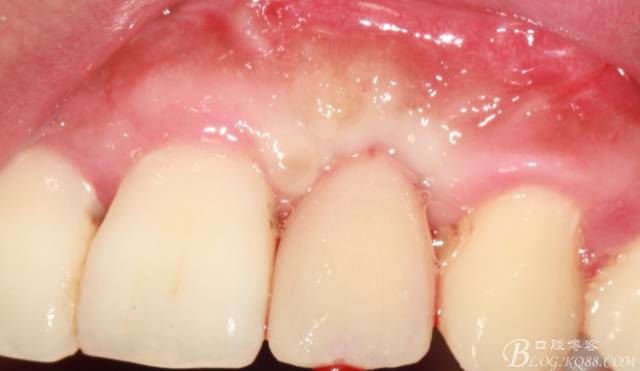

4個月后,唇側(cè)豐滿度尚可,與鄰牙之間齦乳頭完整。

戴入永久修復(fù)體當(dāng)天口內(nèi)照,雖有小瑕疵,但患者很滿意。